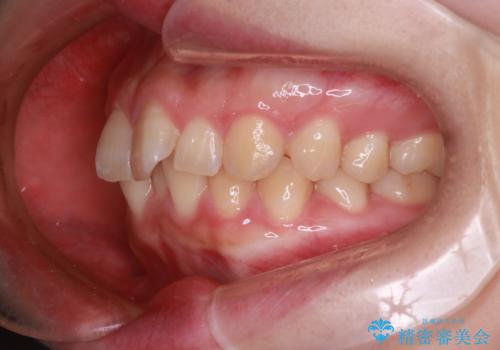

【インビザライン】前歯が出てるのを治したい

- 前歯の凸凹と前突を主訴に来院されました。

インビザラインにて治療をおこない、歯並びを改善することができました。